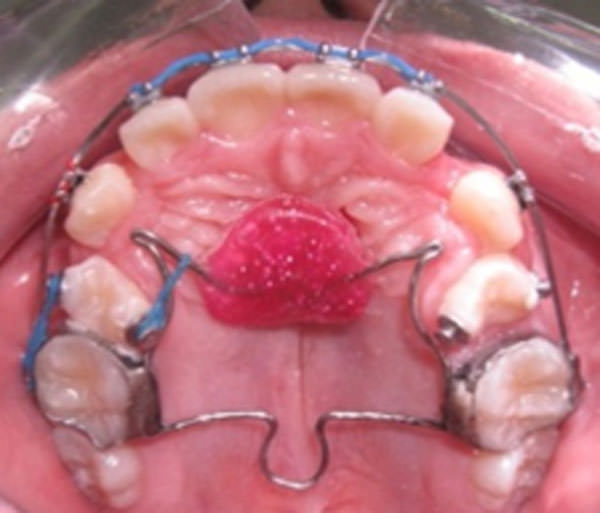

Tratamiento en cuanto a la mecánica, se utilizó un aparato transpalanance con ganchos modificados para el uso de cadenas elastoméricas unidas a botones metálicos bondeados en los segundos premolares superiores (15 y 25) mediante una cupla para permitir desrotarlos. Figura 6 se observa el espacio obtenido de la extracción de los primeros premolares maxilares y la colocación del transpalanance (arco transpalatino modificado con botón de Nance) y el inicio de la alineación y nivelación. En la figura 7, muestra la desrotación de los segundos premolares mediante el uso de modificaciones en el transpalanance y el uso de botones bondeables a los premolares y cadenas elastoméricas. Figura 8, se continua con la mecánica de desrotación, alineación y nivelación, y en la figura 9, se ve la casi total desrotación de los segundo premolares maxilares.

Figuras 6

Extracción de primeros premolares

Figuras 7

Desrotación de segundos premolares